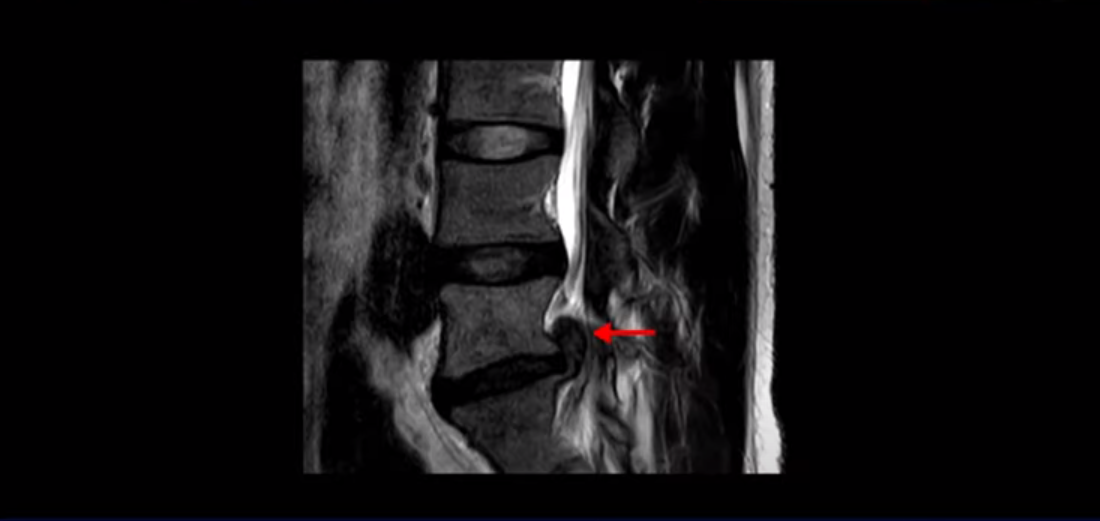

MRI를 보면 이분 5번 1번 디스크가 심하게 터져서 밀려 올라가 있습니다.

이분은 파열이 오른쪽으로 치우쳐 신경이 빠져나가는 추간공을 완전히 막고 있습니다.

다른 신경 구멍들은 열려있는데 비해 5번 1번 구멍은 까맣게 막혀있습니다.

이렇게 심하게 신경가지가 눌리니까 극심한 통증은 당연하고 발목에 마비가 생겨 힘이 빠지는 족하수 증상까지 생겼습니다.